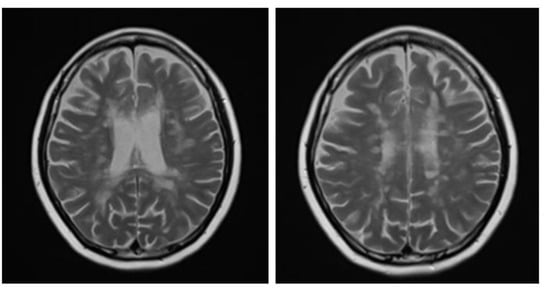

A brain MRI was available for all 32 patients, all of whom showed abnormalities. Most of the patients (19, 59.4%) were subjected to MRI soon after clinical presentation and during follow-up. The lesions were most commonly identified in the periventricular regions (78.1%), juxtacortical regions (75%) and deep white matter (62.5%). Cortical lesions were identified in only eight patients (25%). Other locations included in the McDonald criteria (2017) were the brainstem and cerebellum, which were found in 59.4 and 21.9% of all patients, respectively. The most common characteristic of the lesions was a round/oval discrete appearance (29 patients, 90.6%). A T1W-blackhole and classic Dawson’s finger (Figure 1) were equally identified in 20 patients (62.5%). A tumefactive form was found in two patients (Figure 2 and Figure 3). There were also two patients with target-like lesions, resembling Balo’s concentric sclerosis (Figure 4). The maximal diameter of the lesions was most commonly less than 13 mm (34.4%). A few patients showed lesions measuring more than 52 mm (9.4%), particularly those with confluent lesions. The total number of lesions in the T2W images was most commonly counted at less than 23 (50.0%), while there were up to four patients with extensive lesions, or more than 47 (12.5%) (Figure 5). Gadolinium-enhancing lesions were identified in nine patients (28.1%), who mostly only had one or two of these lesions (in five out of nine patients). Of these, the most common enhancing pattern was nodular enhancement (in four patients). The classic incomplete ring enhancement was identified in two patients, while complete ring enhancement was found in one patient. A visual assessment of the brain volume found brain atrophy in four patients (12.5%). Two patients with tumefactive MS showed brain swelling (Table 2).

Figure 1.

Sagittal fluid attenuated inversion recovery (FLAIR) image shows lesions perpendicular to lateral ventricle giving classic finger-like appearance, Dawson’s fingers.

Axial T2W images of the same patient showing extensive hypersignal–intensity lesions scattered at juxtacortical region, subcortical region, deep white matter and periventricular white matter of bilateral cerebral hemispheres.